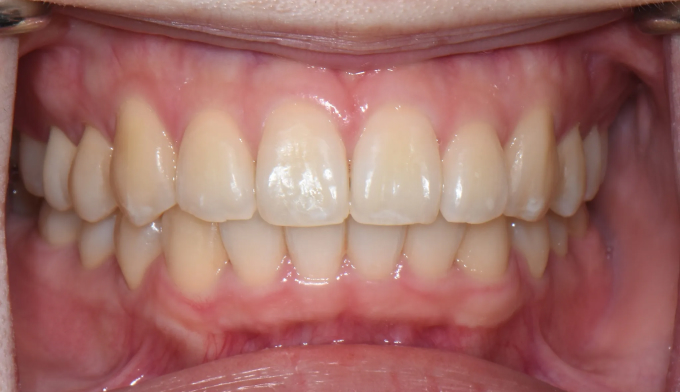

After

윗니는 아랫니를 약 2mm 내외로 덮는것이 심미적으로, 그리고 기능적으로 제일 이상적입니다. 하지만 여러 요인으로 인해 윗니가 아랫니를 절반이상 덮는 경우를 과개교합이라고 부릅니다.

과개교합은 윗니에 무리한 힘이 가해지게 될 수 있고, 앞니의 마모 속도 또한 빨라질 수 있으며 이는 턱관절 문제까지 이어질 수 있습니다.

총 교정기간은 19개월입니다.